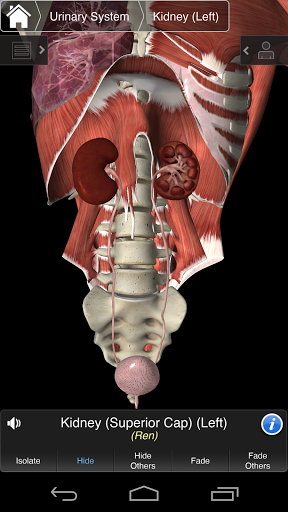

⁃Urinary

Essential Anatomy 3 is responsive, visually stunning and effortless. The app is fully 3D, meaning that you can view any anatomic structure in isolation, as well as from any angle.

---- Multiple Selection Mode - Hide/Fade/Isolate individual or multiple structures

---- Correct audio pronunciation for every structure

---- Latin nomenclature for each anatomical structure